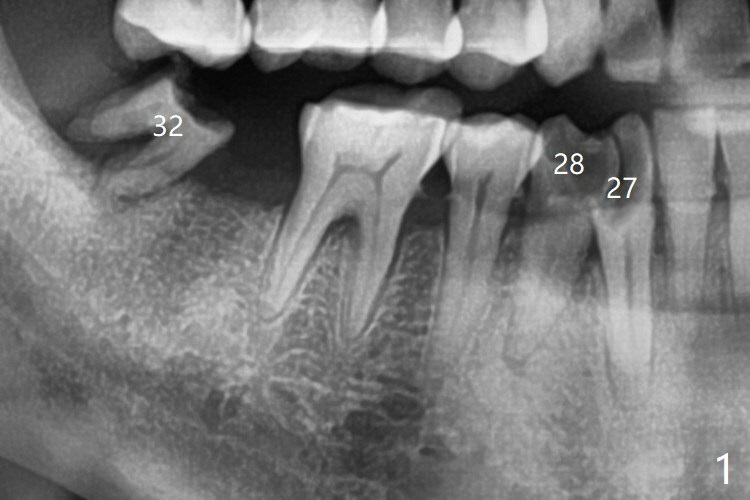

拔除32号牙时发现它接近31区(将要植牙),必须植骨(近中部分(远中塞入胶原塞)),27,28颊侧骨板缺失(大量肉芽组织),植骨理所应当,而且必须拼命推压,但愿推到颊侧骨板,细的皮质骨没有压制感,非要加入粗的松质骨皮质骨,一张12x12毫米胎盘膜剪成两片覆盖27/28和32拔牙窝,4-0 PGA缝线固定,拍摄术后半侧全景片后(图二 (*:骨粉)),使用牙周敷料保护伤口。27/28重叠,近远中8.11毫米,可以植入一个植体,做悬臂桥,或者植入两者之间。The bone graft remains in place 1 month postop (Fig.8).  术后一个月27,28号牙位骨粉保持原位(图八)。